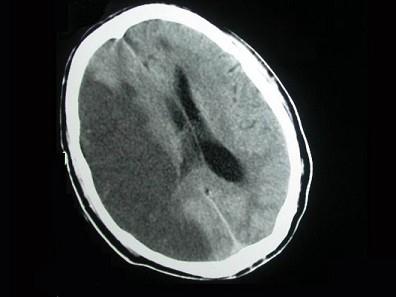

问题 患者,80岁,有高血压病史10年,糖尿病5年,突发一侧肢体无力伴昏睡2天入院,行头颅CT出现如图所示脑梗死,该病灶最可能是下列哪条阻塞引起 ( )

选项 A、脉络膜前动脉 B、大脑中动脉深穿支 C、颈内动脉主干或大脑中动脉主干 D、大脑中动脉主干或大脑后动脉 E、大脑前动脉主干或大脑中动脉主干 一、单项选择题

答案 C